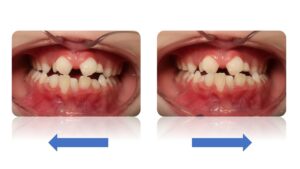

La classes II subdivision fonctionnelle est la conséquence d’une mastication préférentielle voir exclusivement unilatérale. Cette dysfonction engendre alors une bascule du plan d’occlusion dans le plan frontal mais également dans le plan vertical et sagittal.

L’orthodontie systémique permet d’appréhender cette pathologie par l’analyse des latéralités mandibulaires (AFMP).

Le traitement qui en découle est donc fonctionnel et stable car il permet une réorientation du plan occlusal, symétrisant ainsi les AFMP et donc la mastication.

C’est donc la fonction qui joue le rôle de contention des traitements systémiques.